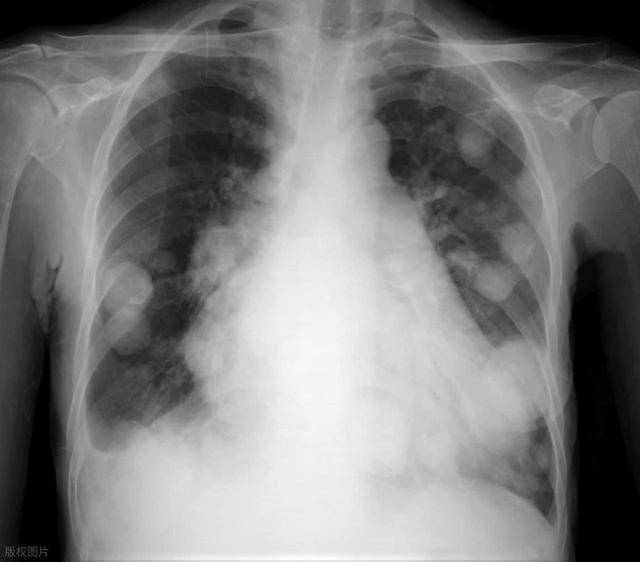

然而,约5%-10%的肺结节可能存在恶性风险,是早期肺癌或癌前病变的表现。因此,“盯紧”它,通过科学的随访观察其变化,是区分良恶性、早期发现肺癌的关键。

-   磨玻璃结节的特殊性:磨玻璃结节(GGN)是一种特殊的肺结节类型,其恶性风险相对较高,尤其是持续存在的纯磨玻璃结节或部分实性磨玻璃结节。这类结节的恶变过程往往较为缓慢,“按年计算”。

-   重新评估的机会:一年后的复查可以观察结节在较长时间内的变化。如果一年内结节依然稳定,无增大、密度无增加、边缘无明显变化,则良性可能性进一步增加。若出现轻微形态改变(如边缘模糊、密度加深、出现实性成分),则需提高警惕。